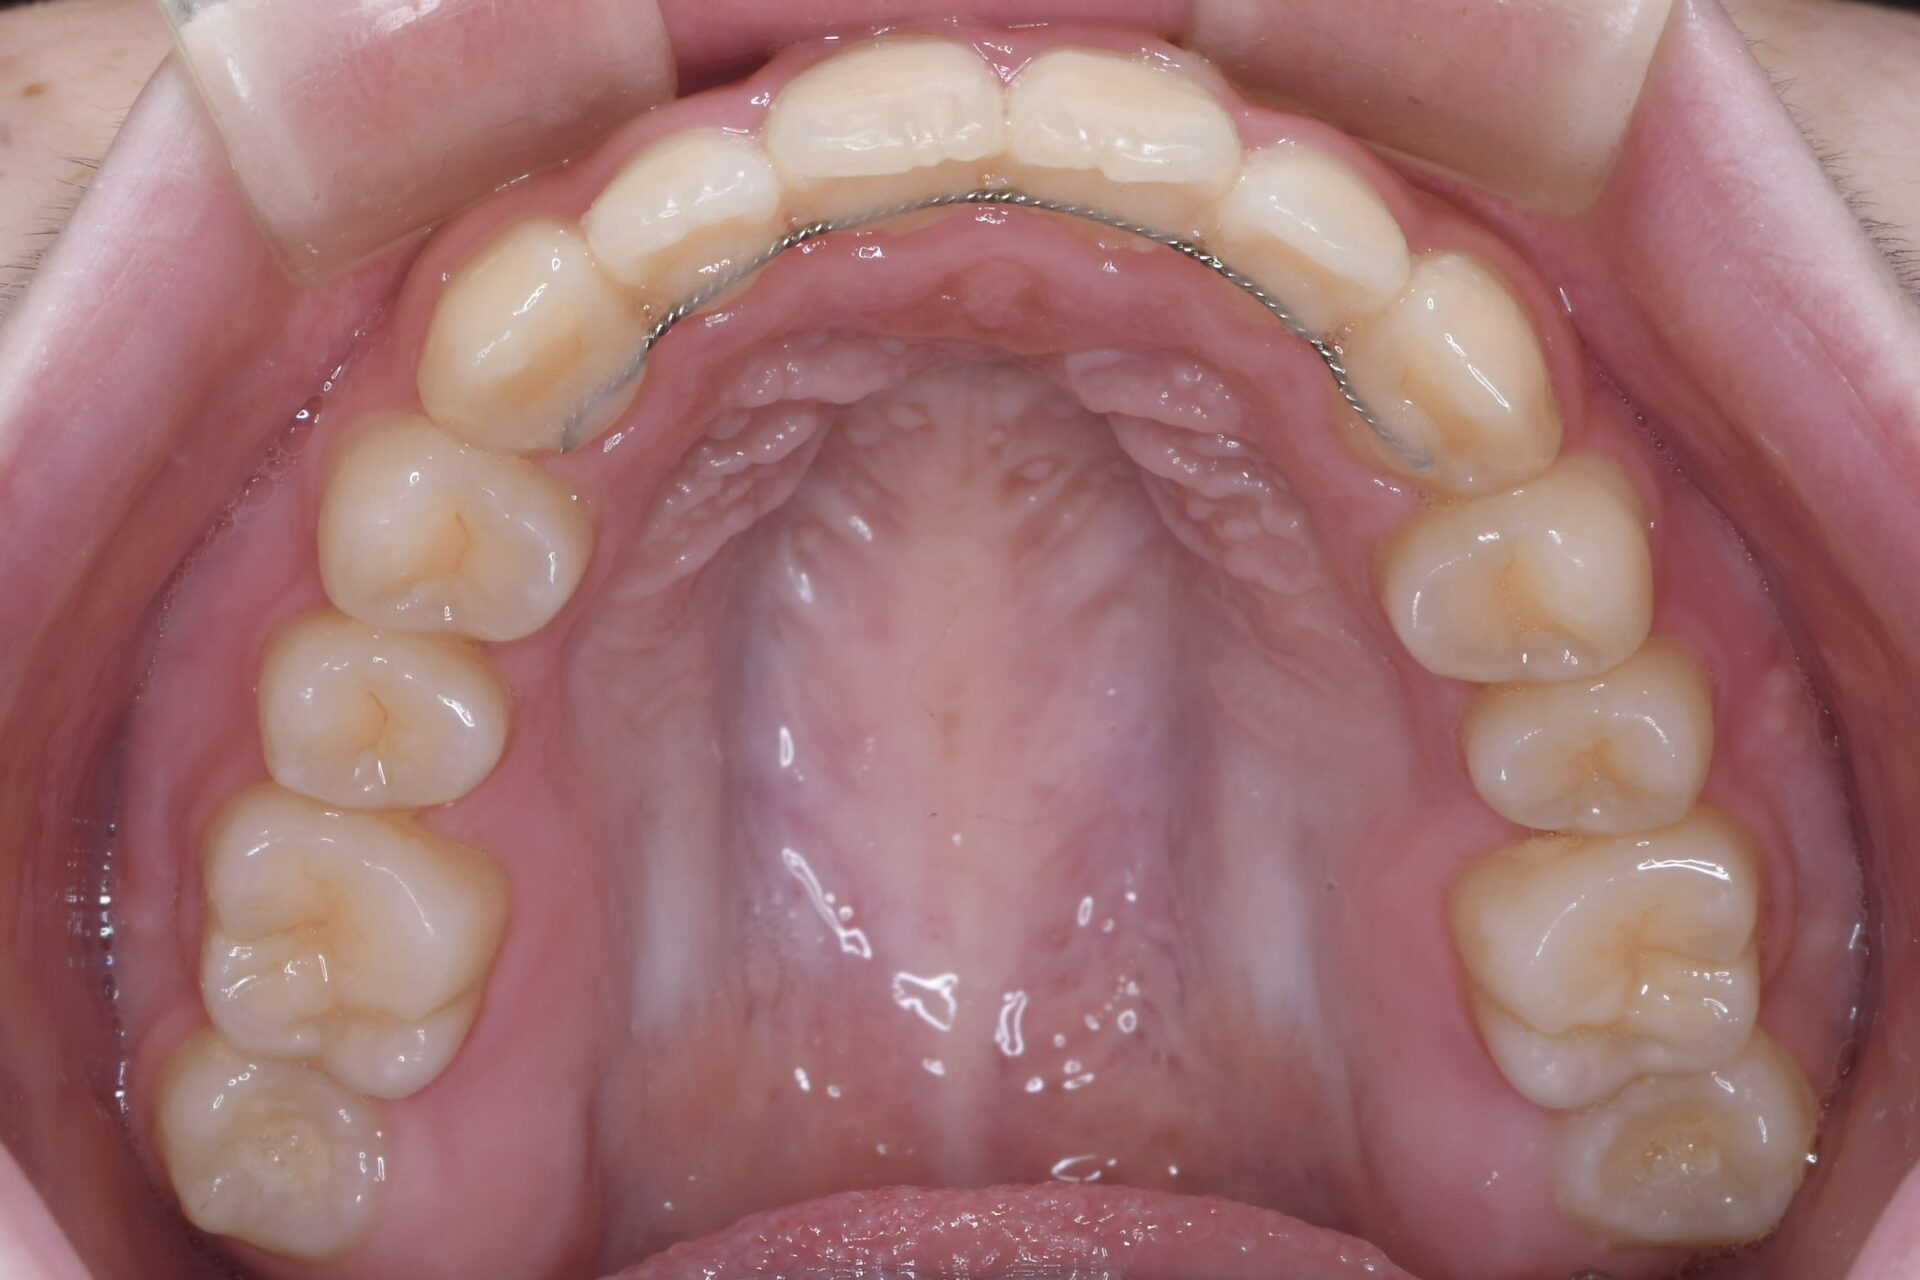

メインテナンス時(上顎)